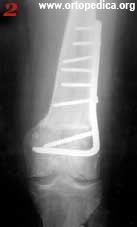

2. Рентгенограмма больного Л. после операции коррегирующей остеотомии дистальной трети бедренной кости